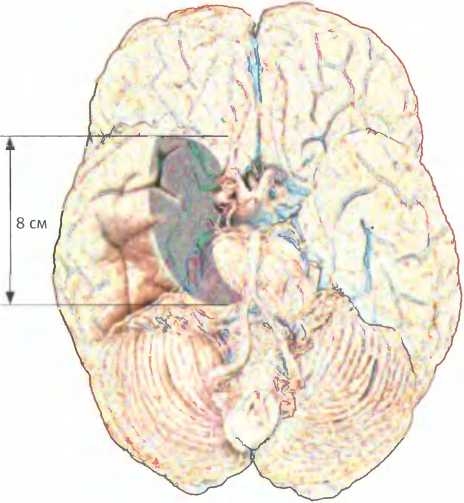

Удаленные в обоих полушариях участки включали передние две трети гиппокампа, зону окружающей ткани размерами около 8 х 6 см и миндалину10.

По мере развития болезни Альцгеймера мозг сморщивается и уменьшается в размерах. Здоровый мозг [слева) и мозг человека с ярко выраженными симптомами болезни Альцгеймера (справа).